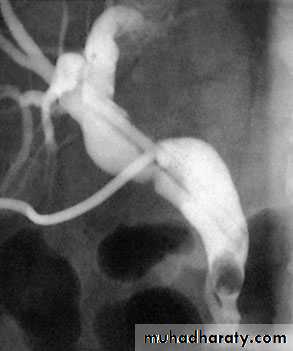

66Transhepatic cholangiogram showing a stricture of thecommon hepatic duct